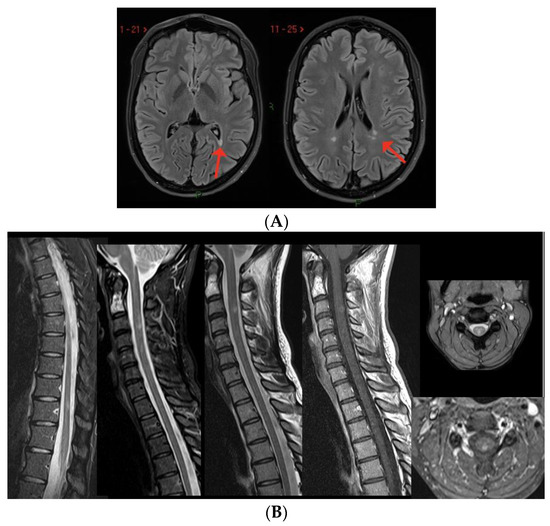

5. MS Relapses after Vaccine Exposure